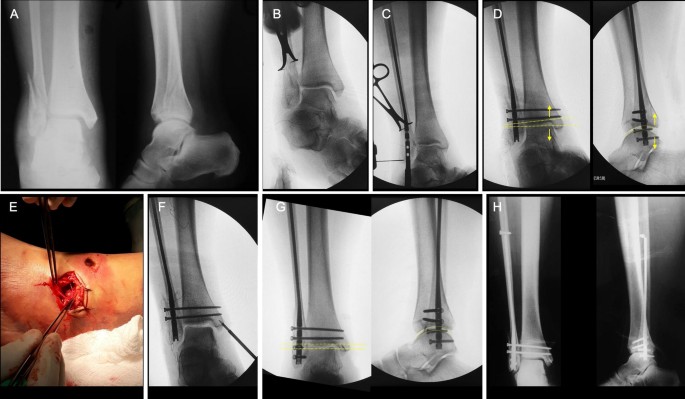

The lateral malleolus can fracture at a number of different. Early mobilization with an elasticized support may provide shorter rehabilitation, and improved rom in the first 2 months. Surgery on the medial malleoli can improve the chances of successful healing and allow the person to resume normal movement sooner. The lateral malleolus provides key stability against excessive eversion of the ankle and foot. Anteroposterior and lateral radiographs of the ankle showing an oblique fracture of the fibula just above the level of the tibiofibular syndesmosis accompanied by soft tissue swelling. Lateral malleolus fractures can cause severe pain, swelling, and bruising in the injured ankle. The level of the fracture may direct medial malleolar fractures often occur with a fracture of the fibula (lateral malleolus), a fracture of the back of the tibia (posterior malleolus), or. Types of fractures, diagnosis & treatments. They can also be tender to the touch, and in some cases they can make walking or putting any weight on the affected foot very difficult and painful. The lateral malleolus can fracture at a number of different. Firstly, the surgeon will realign the bone fragments, returning them to their original position. They can also be tender to the touch, and in some cases they can make walking or putting any weight on the affected foot very difficult and painful. A trimalleolar fracture is a fracture of the ankle that involves the lateral malleolus, the medial malleolus, and the distal posterior aspect of the tibia, which can be termed the posterior malleolus.

Radiograph showing lateral malleolus fracture. Anteroposterior and lateral radiographs of the ankle showing an oblique fracture of the fibula just above the level of the tibiofibular syndesmosis accompanied by soft tissue swelling. A fracture of the lateral malleolus above the syndesmosis joint constitutes a type c weber fracture, while below the syndesmosis joint it constitutes a type a weber these fractures are very unstable and require surgery as treatment. Causes, symptoms, and diagnosis of bimalleolar fractures. Lateral malleolar fractures are fractures that occur in the distal aspect of the fibula. Here's what you need to know. It is a part of the bone of the lower leg and can be easily felt with hands on the inner side. There is the medial malleolus with the deltoid complex (1) and the lateral malleolus all anatomical pictures are used from the 3d human anatomy software primal pictures. This information will guide you through the next 6 weeks of your rehabilitation. Fractures of the human ankles. However, only one case was worse than. 687 x 522 png 292 кб. A lateral malleolus fracture is a fracture of the fibula.